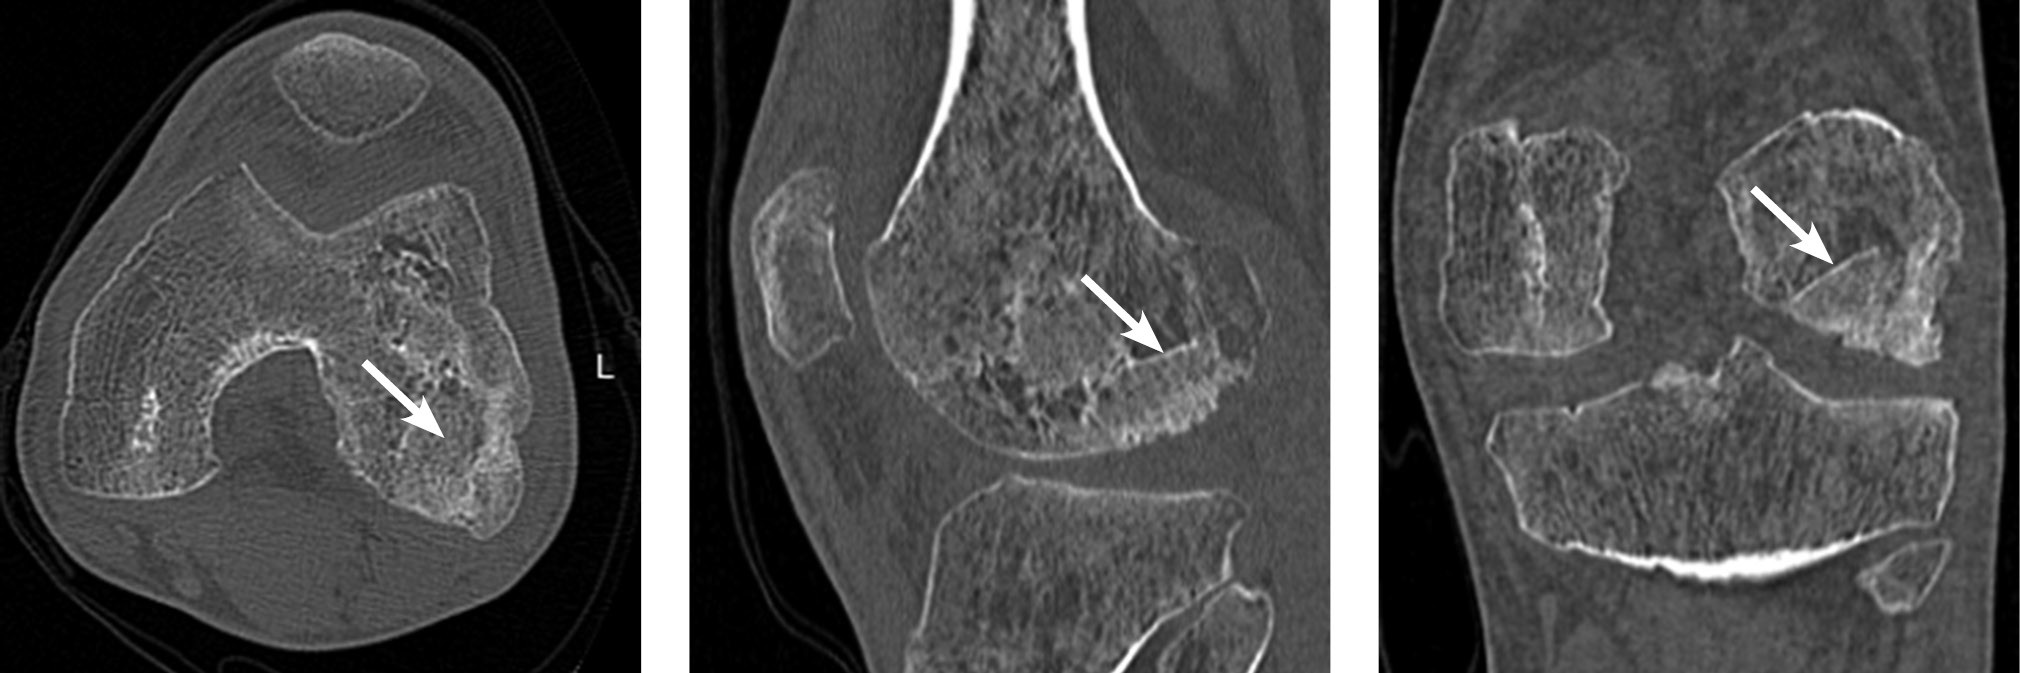

Imaging examinations revealed an osteochondral destruction zone in the lateral condyle of the left femur measuring 3.3 × 2.8 × 1.5 cm, along with a loose osteochondral body measuring 2.2 × 2 × 0.5 cm (ICRS grade IV). The imaging findings are shown in Figure 5.

Fig. 5. Imaging of patient M.: a, magnetic resonance imaging, sagittal slice; b, spiral computed tomography, sagittal slice through the osteochondral defect of the lateral femoral condyle; c, spiral computed tomography, 3D reconstruction illustrating the size of the defect and the presence of a loose osteochondral fragment in the lateral femoral condyle. Arrows indicate the osteochondral defect region and the loose osteochondral fragment.

Follow-up computed tomography revealed full consolidation and integration of the bone graft (Fig. 7).

Fig. 7. Patient M. Computed tomography of the left knee joint with three standard projections. The bone graft zone is indicated by an arrow.